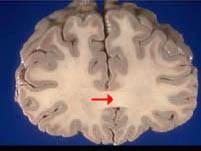

如图箭头所示为大脑哪个部位 ( )A、穹窿B、中脑导水管C、胼胝体D、透明隔E、前连合一、单项选择题

问题 如图箭头所示为大脑哪个部位 ( )

选项 A、穹窿 B、中脑导水管 C、胼胝体 D、透明隔 E、前连合 一、单项选择题

答案 C